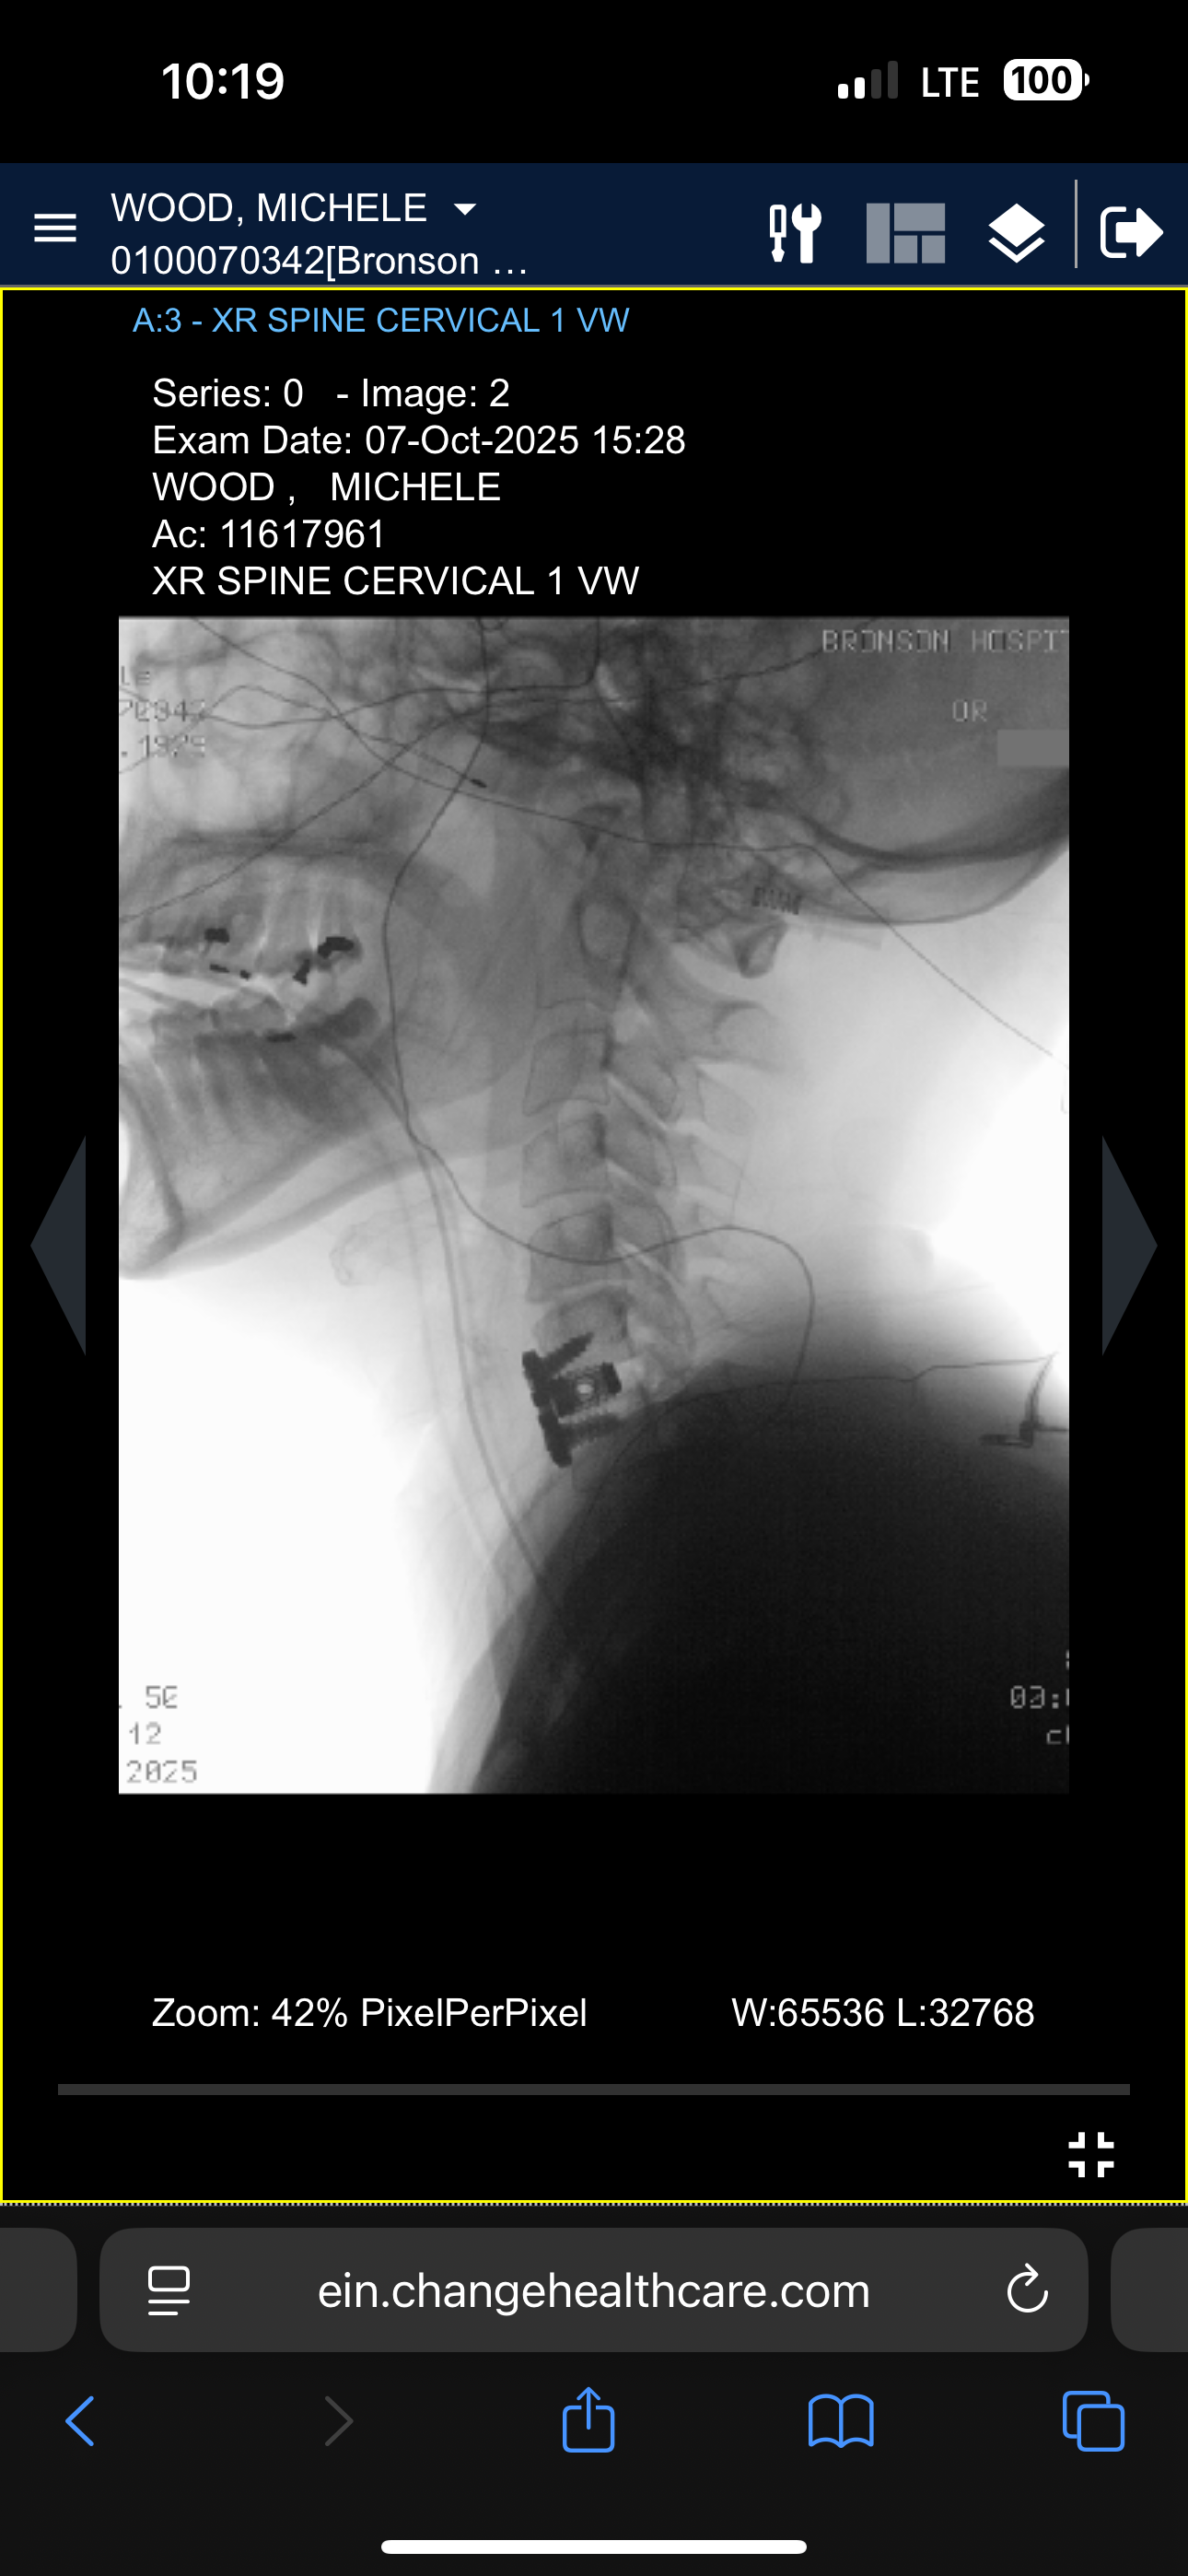

For over a year, I've had a pain in my neck and right shoulder blade. I thought I pulled something. Fast forward to May of this year. X-rays showed a narrowing of my cervical spine. I was sent to physical therapy. After 8 weeks of no relief, the PT recommended I have a follow-up appointment with my primary provider. Then they ordered an MRI. The results showed nerve damage caused by the degeneration of my C6-C7. I was then referred to a neurosurgeon at Bronson Methodist. The neurosurgeon recommended a fusion surgery that will most definitely help me. My surgery is scheduled for October 7.